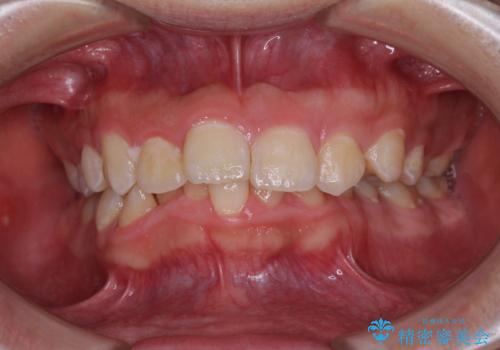

- デコボコと奥歯の咬み合わせのズレを気にして来院された患者様です。

骨格的に、下顎が右側にずれており、左側の咬み合わせに鋏状咬合などのアンバランスが生じている状態でした。

また、上顎前歯に欠損が1本あり、上下ともに前歯部に叢生が認められ、下顎前歯の大半が隠れてしまうほどの過蓋咬合も認められました。